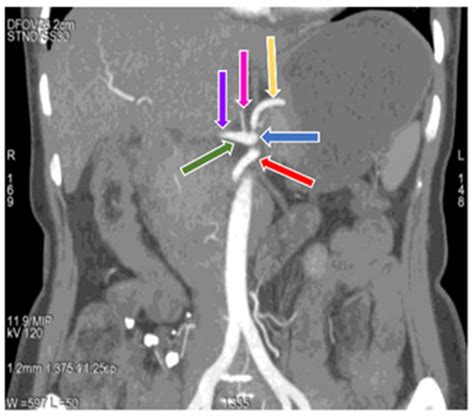

The human abdominal anatomy is a complex network of vessels, and understanding the branches of celiac axis—often referred to as the celiac trunk—is fundamental for medical students, radiologists, and surgeons alike. As the primary arterial supply for the foregut, the celiac trunk is a short, wide artery that originates from the abdominal aorta at the level of the T12 vertebrae. Its role in delivering oxygenated blood to vital organs, including the stomach, liver, spleen, and pancreas, cannot be overstated. By studying the branching patterns, clinicians can better diagnose vascular pathologies and navigate the abdominal cavity during surgical interventions.

The celiac axis is the first major anterior branch of the abdominal aorta. It is remarkably short, typically measuring between 1 to 2 centimeters before it divides into its three primary vessels. The anatomical orientation of the branches of celiac axis follows a specific pattern that ensures the upper abdominal viscera receive continuous perfusion. Understanding this “tripod” configuration—known as the tripus Halleri—is essential for identifying the standard anatomy versus common anatomical variations that can complicate medical procedures.

The classic description of the celiac trunk involves a trifurcation into three distinct arteries. Each of these branches supplies specific organs, forming a collateral network that protects the foregut from ischemia. The primary branches are as follows:

• Left Gastric Artery: Often considered the smallest of the three, it travels superiorly toward the esophagus and then descends along the lesser curvature of the stomach.

• Common Hepatic Artery: This vessel travels to the right, serving as the gateway to the liver, gallbladder, and parts of the stomach and duodenum.

• Splenic Artery: Typically the largest branch, it follows a tortuous path along the superior border of the pancreas toward the spleen.

Clinical Relevance in Modern Medicine

💡 Note: When reviewing diagnostic images, pay close attention to the takeoff angle of the celiac trunk, as sharp angulation can be an early indicator of vascular compression syndromes.